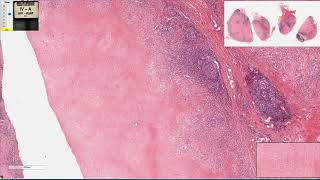

por HR né então quem corre o núcleo é hematoxilina que aquele corante roxo que tem afinidade por estruturas mais ácidas você acaba gerando uma área de maior condensação nuclear então núcleo se condensa geralmente pelos processos regressivos metabólicos onde é uma mudança de PH gerando um acidificação desse núcleo você acaba tendo um é super kromasil nuclear ou seja se não colocava corando fortemente pela hematoxilina e se tornando pequeno esse fenômeno a gente chama de picnose então a gente observa aqui comparando com essas células do baço normais a gente percebe esse núcleo mais condensado aqui embaixo a

gente percebe outra característica que é a fragmentação desse núcleo estão a fragmentação nuclear a gente chama de cariorrexe por fim a liso e também dessas ela leva uma cariólise completa cariólise portanto seria o desaparecimento desse núcleo que histologicamente podemos observar pela falta do corante hematoxilina ali naquele tecido naquele tecido Caso seja apurado em h e nessas duas imagens a gente consegue perceber nitidamente isso esse citoplasma eosinofílico ou seja mais rosa um núcleo pequeno e condensado o que notco ou no que eu em picnose a fragmentação do núcleo a cariorrexe e aqui várias células em cariólise

de receber oxigênio portanto geralmente a área ela é piramidal vez eu não tinha aqui a gente também consegue observar uma área bem avermelhada no seu seja É bem delimitada por um Halo eritematoso ou hiperêmico isso representa o processo inflamatório intenso que a região sendo gerada pelo próprio processo necrótico e histologicamente falando nós temos aqui duas áreas bem distintas nessa lâmina nesse lado a gente consegue perceber um ausência da hematoxilina hora que que significa que eu praticamente não tem núcleo nessa região que é aquela característica muito clara da necrose que era a cariólise não é percebam

que a picnose ela ainda pode ser observada naqueles eventos celulares ainda reversíveis a partir do momento que isso vai gerando uma cariorrexis a fragmentação EA sua dissolução completa esse evento tá mais claro No que diz respeito à necrose mas percebam também que a gente pode que a gente mantém aqui arquitetura desse órgão é um rim portanto ainda consigo perceber alguns túbulos renais algumas áreas glomerulares nas absolutamente anucleado essa região toda é uma região e essa região que faz essa interface aqui esse front é uma região com uma grande quantidade de hematoxilina ou seja gente percebe

muito roxinho aqui né pontos que representam nossos núcleos tanto núcleo também em picnose o encare o reflexo do próprio processo de necrose que tá acontecendo ali naquela faixa mas também núcleos relativos aí as células inflamatórias que estão chegando em filtrando esse local então a principal característica da necrose coagulativa é a perda nuclear a intensa eu zoofilia e a manutenção da arquitetura no do órgão num primeiro momento nesta segunda imagem a gente percebe uma peça na croscop cadê um coração de um miocárdio onde a gente a gente observa todo uma área isquêmica aqui de necrose coagulativa